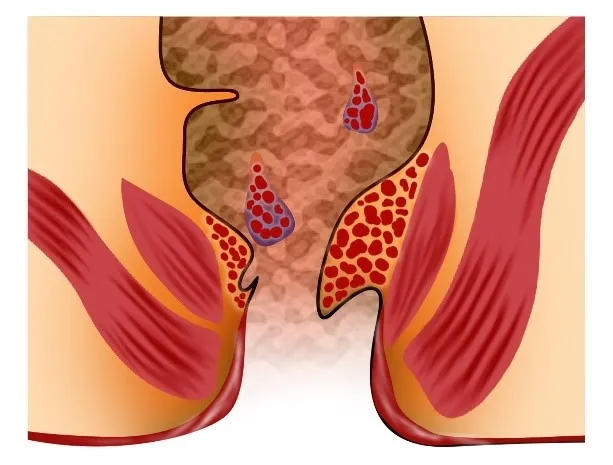

Seeing blood during passing stool can be frightening ...

ਬਵਾਸੀਰ (ਹੈਮੋਰਾਇਡਸ) ਗੁਦਾ ਅਤੇ ਮਲਦਵਾਰ ਦੀਆਂ ਸੋਜੀ ਹੋਈਆਂ ਰਗਾਂ ਹਨ ...